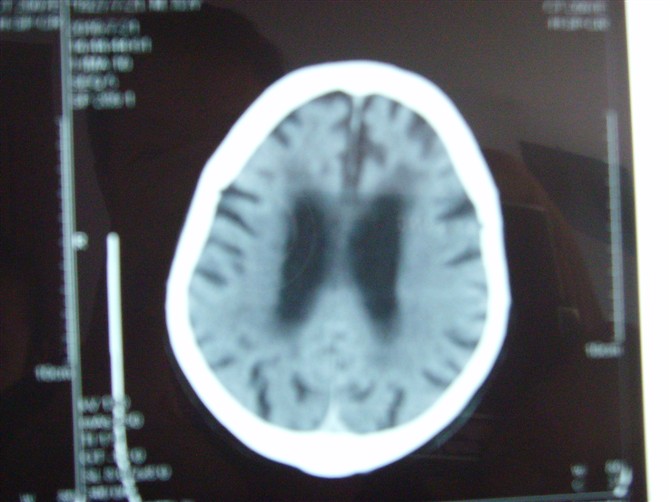

标题: CT27993:男 83岁 头晕伴双下肢无力一天 [打印本页]

标题: CT27993:男 83岁 头晕伴双下肢无力一天

脑白质疏松症,脑萎缩,复查

脑萎缩。伴小脑齿状核、苍白球钙化.脑白质脱髓鞘病变

脑萎缩,脑白质疏松症。

1)双侧小脑半球脑软化灶。2)全脑萎缩。3)脑白质病。